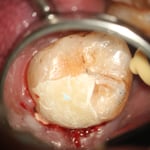

写真はすべてミラー像です。上顎左側側切歯遠心面の大きな虫歯です。エキスカで丁寧に軟化象牙質を除去していくと、歯髄腔まで本当に皮一枚になりました。血流が見えるようです。エキスカから伝わる組織の硬軟の感覚と対物-接眼レンズからの像が ”皮一枚”を達成できたと思います。皮一枚ですが、硬組織は残っていますので、ティース・プライマーを塗布し、スーパーボンド・ラジオオペークとバルクベースにて覆髄をしました。もちろん、1ケ月後の歯髄診でも陽性反応を示し、歯髄は生きています。